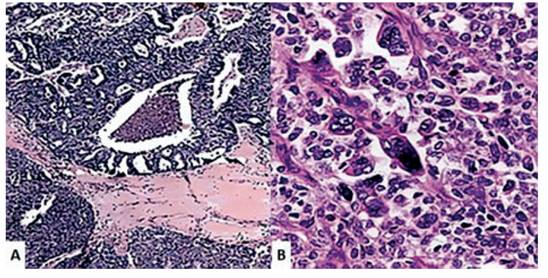

El estudio anatomopatológico reveló que la trompa de Falopio derecha presentaba una tumoración principalmente sólida con superficie de 7 x 5 x 4 cm entre la ampolla y el istmo. Varios quistes de paredes finas de 0,5 a 20 milímetros cubrían su superficie (figura 2). La fimbria tenía consistencia blanda a gomosa con luz ocluida por una zona grisácea-azulada, sin presencia de tumores. Al examen microscópico, el tumor mostraba un patrón de crecimiento papilar amplio con septos fibrosos, nidos y papilas celulares poligonales atípicas, así como espacios microquísticos perforados y áreas de necrosis en parches (figura 3). Además, los núcleos de las células tumorales tenían surcos nucleares prominentes con más de 20 mitosis por 10 campos de alta potencia. No hubo evidencia de células tumorales en el líquido de lavado peritoneal. La tinción inmunohistoquímica mostró una señal positiva para CK7 y el antígeno de la membrana epitelial, mientras que la tinción fue negativa para p53, CK20 y p63. Los hallazgos histológicos confirmaron el diagnóstico de carcinoma primario de células transicionales de trompa de Falopio.

Figura 3 imágenes de anatomía patológica del carcinoma de células transicionales de la trompa de falopio. a) células neoplásicas que forman laminas y trabéculas y áreas de necrosis en parche (coloración hematoxilina-eosina, 40x). b) células poligonales atípicas formando nidos y papilas (coloración hematoxilina-eosina, 400x).